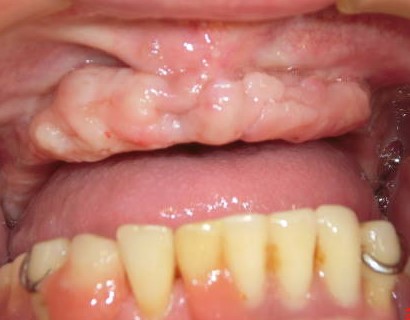

症例1:67歳男性

総義歯が安定しないため、義歯性線維腫の切除を行いました。

義歯床縁をおおうように粘膜のヒダができ、粘膜は正常で、触れるとコリコリしたような硬さです。